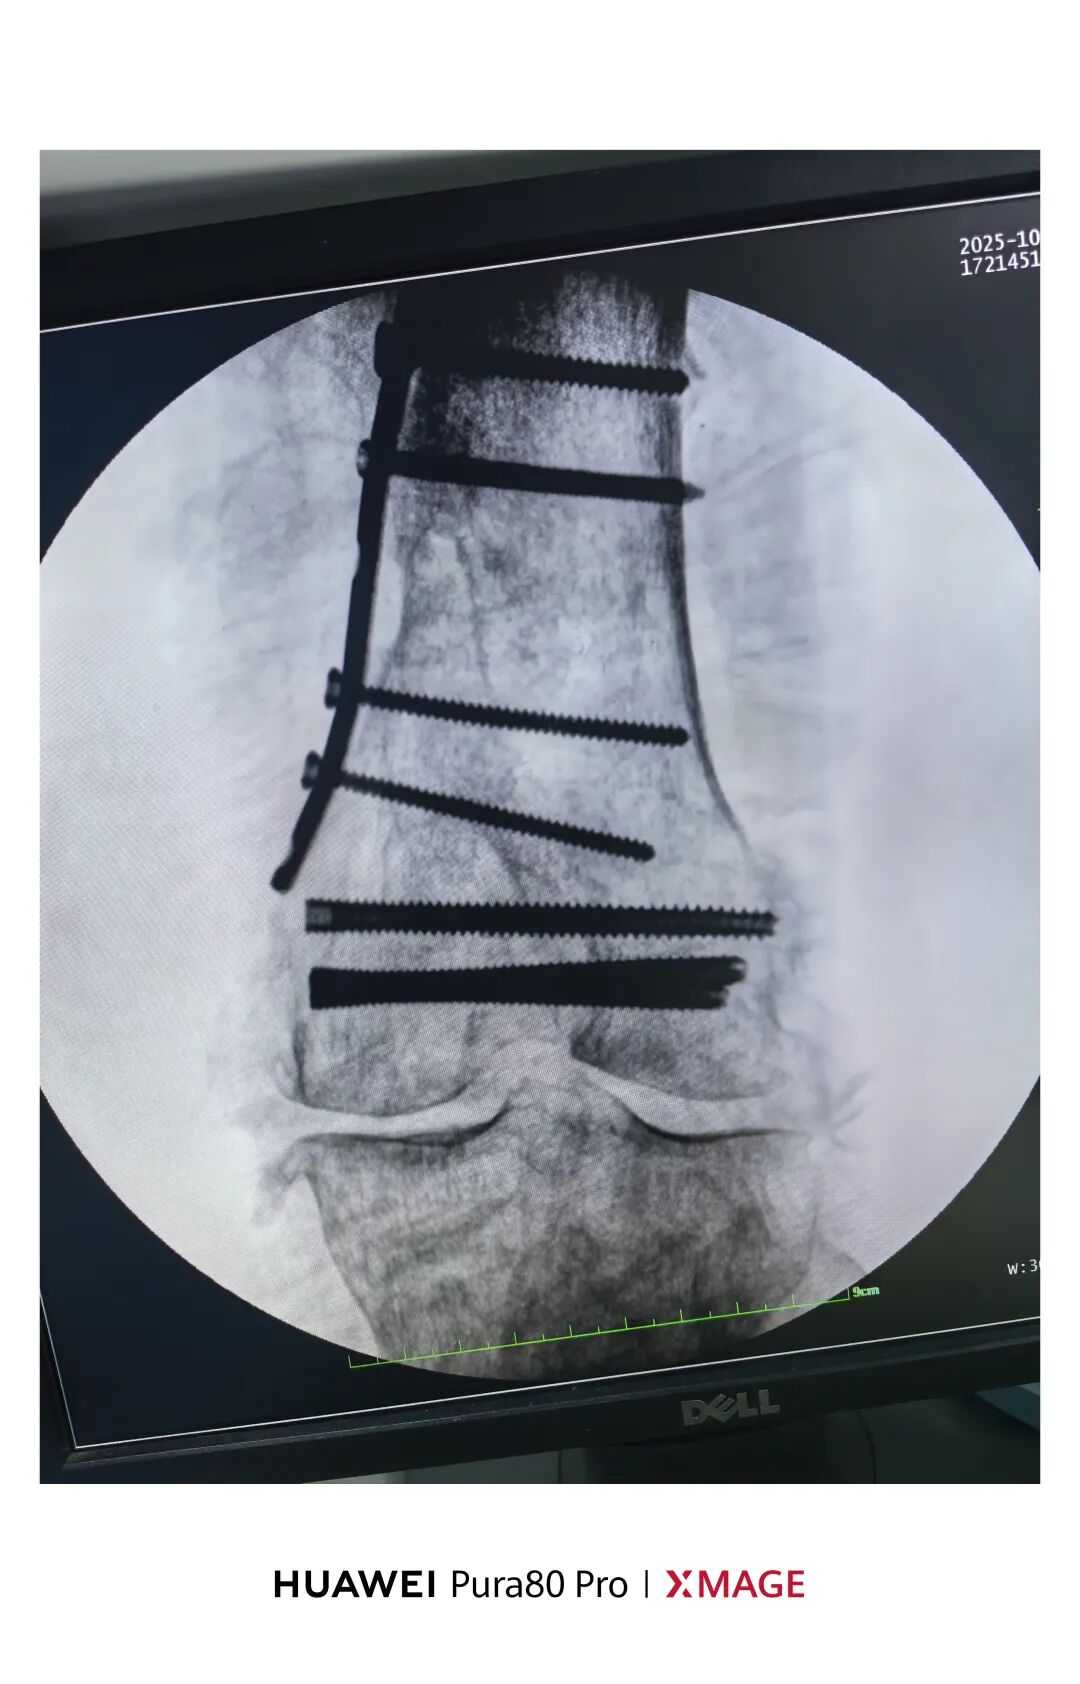

5个月前在魔都骨折,当时建议手术

患者拒绝并签字

给予支具固定

现畸形、疼痛伴活动受限来院

复位满意,力线纠正